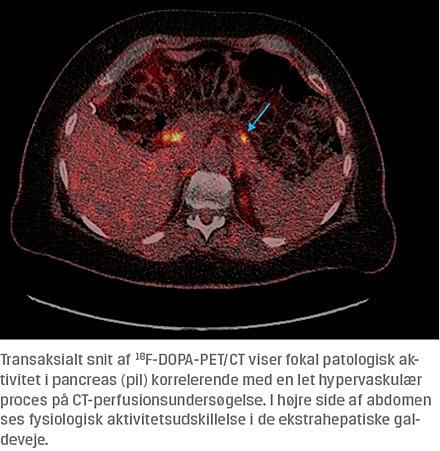

Ved en 18F-DOPA-PET/CT påvistes i pancreas et fokus, som havde patologisk aktivitet og korrelerede med fund af en hypervaskulær proces på en perfusions-CT. Pga. den ændrede anatomi efter GB var det ikke muligt at visualisere eller bioptere processen ved en endoskopisk UL-undersøgelse. Patienten gennemgik en distal pancreasresektion, og ved en efterfølgende patologisk undersøgelse bekræftedes diagnosen: lokaliseret benignt højtdifferentieret insulinom. Ved en genetisk udredning blev der ikke påvist disponerende mutationer. Patientens blodglukoseniveau normaliseredes umiddelbart efter operationen, symptomerne forsvandt, og hun var herefter symptomfri. En efterfølgende fastetest blev gennemført uden hypoglykæmi.

hypoglykæmier efter GB som hos patienten i sygehistorien, hvor hypoglykæmierne også opstod både, når patienten var fastende, og om natten, er det vigtigt at overveje en anden patogenese herunder insulinom, hvor den primære undersøgelse er 72 timers faste (Figur 1). Den efterfølgende lokalisationsdiagnostik er ofte udfordrende, som også illustreret i sygehistorien, hvor fokus først blev klarlagt ved 18F-DOPA-PET/CT med fusion af anatomisk og funktionel information. For år tilbage, da de første svære hypoglykæmier blev beskrevet efter GB, blev det diskuteret, om årsagen var nesidioblastose (excessiv funktion af de pankreatiske betaceller ofte med en grad af hypertrofi og dysplasi) [4]. Det er siden blevet tilbagevist, at dette skulle være en væsentlig årsag, og vi fandt heller ingen tegn på det. GB-operationen synes således ikke at have være årsagen til udvikling af insulinomet hos patienten i sygehistorien. Blandt op mod hundrede patienter med hypoglykæmi efter GB har vi på Aarhus Universitetshospital ikke fundet andre med insulinom efter GB.